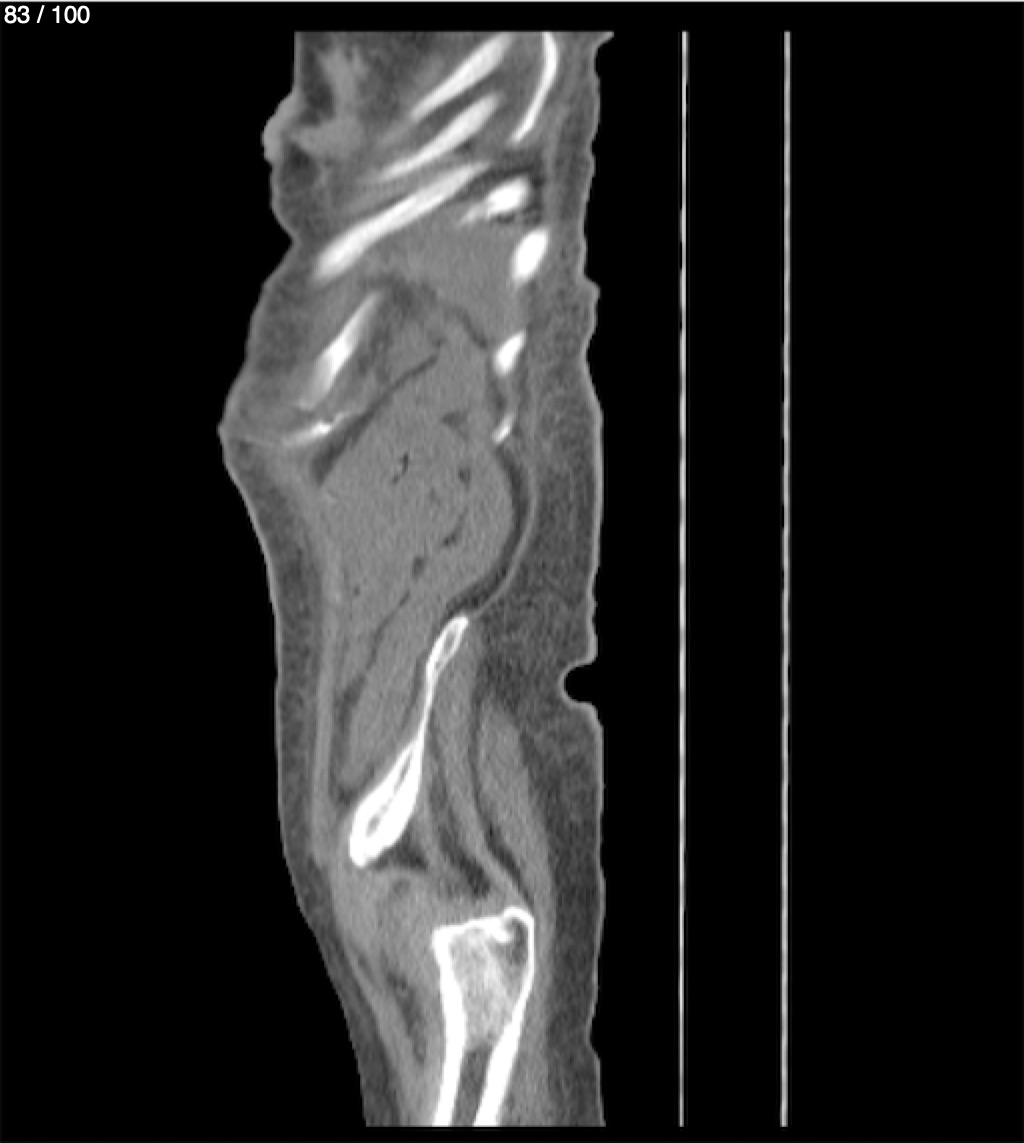

Hilda Geronimo Mendez 60A - T.C Abdomen Simple